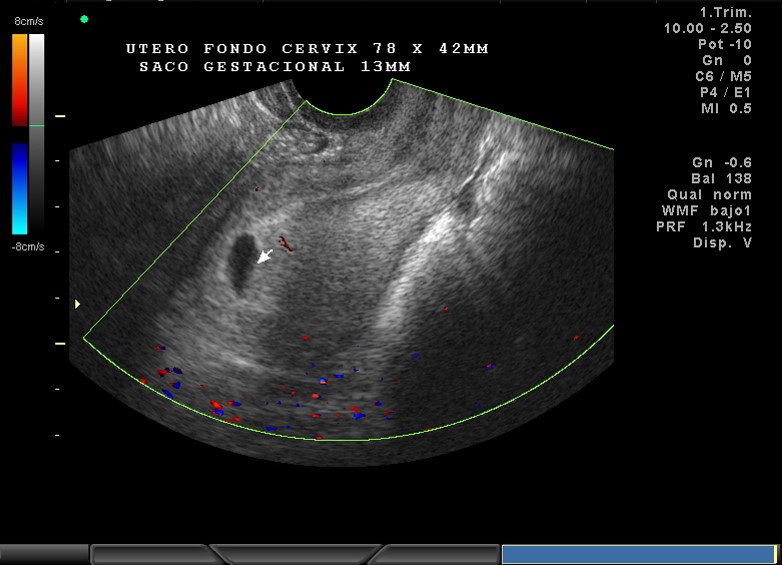

2D Y COLOR, 6.5 SEMANAS DE GESTACION